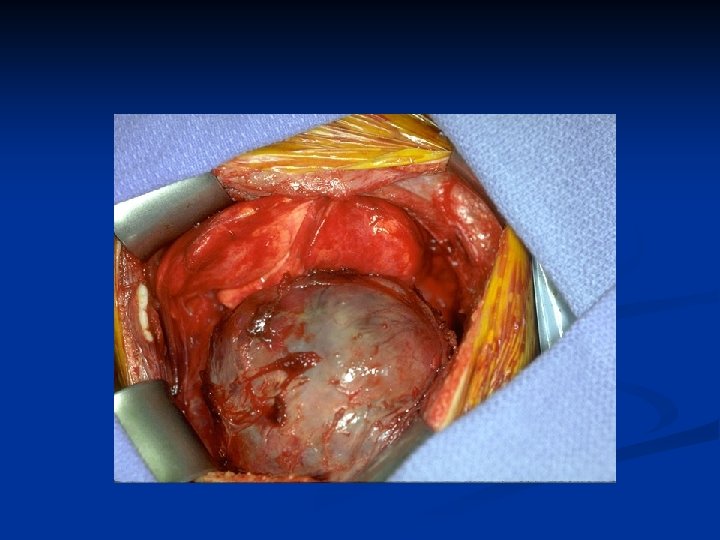

Management n n n Unless extensive metastatic disease it invariably involves surgery Surgical option usually involves a radical nephrectomy Kidney approached through either a transabdominal or loin incision Renal vein ligated early to reduce tumor propagation Kidney and adjacent tissue (adrenal, perinephric fat) excised

Open Radical Nephrectomy